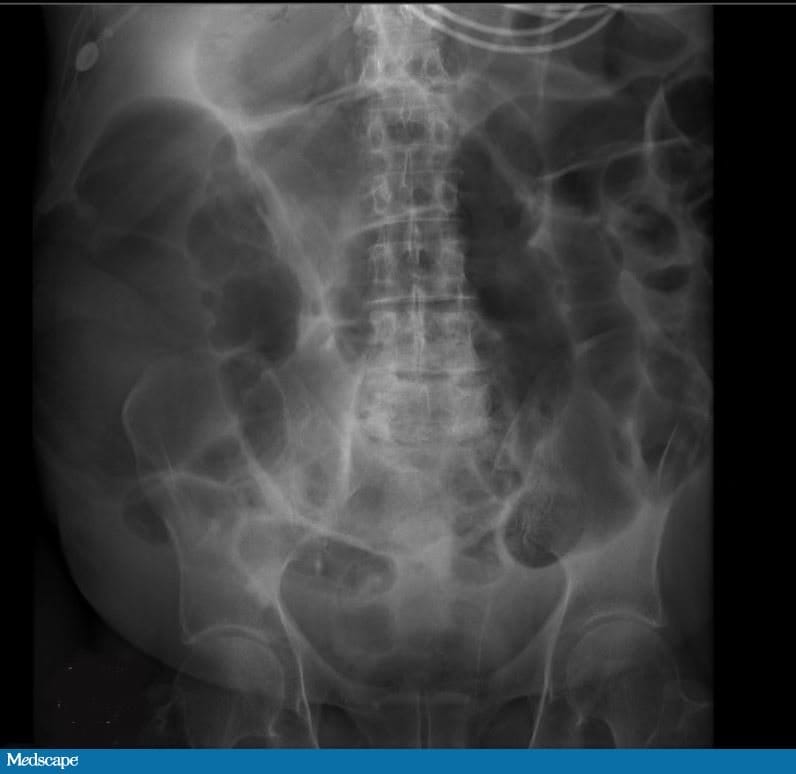

Homem caucasiano de 65 anos chega ao pronto-socorro com grande distensão abdominal. Informa que seu abdome tem estado cada vez mais distendido nos últimos quatro dias. Refere diminuição do apetite e náuseas, sem vômitos. Também descreve desconforto abdominal e leve dor difusa. Relata que a sua última deposição de fezes foi há cinco dias. Está eliminando flatos.

Nega febre, calafrios ou dor torácica. Menciona dificuldade de respirar. A anamnese revela história de hipotireoidismo, que ele trata com levotiroxina. Também foi diagnosticado com doença pulmonar obstrutiva crônica (DPOC) para a qual usa albuterol inalatório, budesonida e formoterol inalatórios. Também apresenta hipertensão arterial sistêmica , para a qual  toma anlodipino, e hiperlipidemia, para a qual toma atorvastatina.

Recentemente foi internado por exacerbação da DPOC e bronquite aguda. A internação foi prolongada (sete dias), e ele foi tratado com metilprednisolona intravenosa, albuterol, budesonida e arformoterol intravenosos. O paciente teve alta domiciliar com prescrição de redução gradual da dose de prednisona oral há quatro dias.

Exame físico e propedêutica

Ao dar entrada no serviço de emergência, o paciente apresenta 37,16 °C de temperatura, frequência cardíaca de 104 batimentos por minuto, frequência respiratória de 22 incursões respiratórias por minuto, pressão arterial de 112 × 84 mmHg e saturação de oxigênio de 92% em ar ambiente.

Ao exame parece desconfortável e está deitado em decúbito dorsal; sua mucosa oral está ressecada. O exame do abdome revela grande distensão abdominal, com leve dor difusa à palpação e sem sinal de descompressão dolorosa nem defesa. Peristalse presente e abdome timpânico. Sua dor abdominal parece desproporcional aos achados do exame físico.

Todos os outros exames laboratoriais estão normais. É feita uma radiografia de abdome. O paciente é internado por causa dos seus exames. Uma tomografia computadorizada (TC) de abdome e pelve sem contraste é feita na sequência. Os achados dos exames de imagem são mostrados abaixo (Figuras 1 a 4).